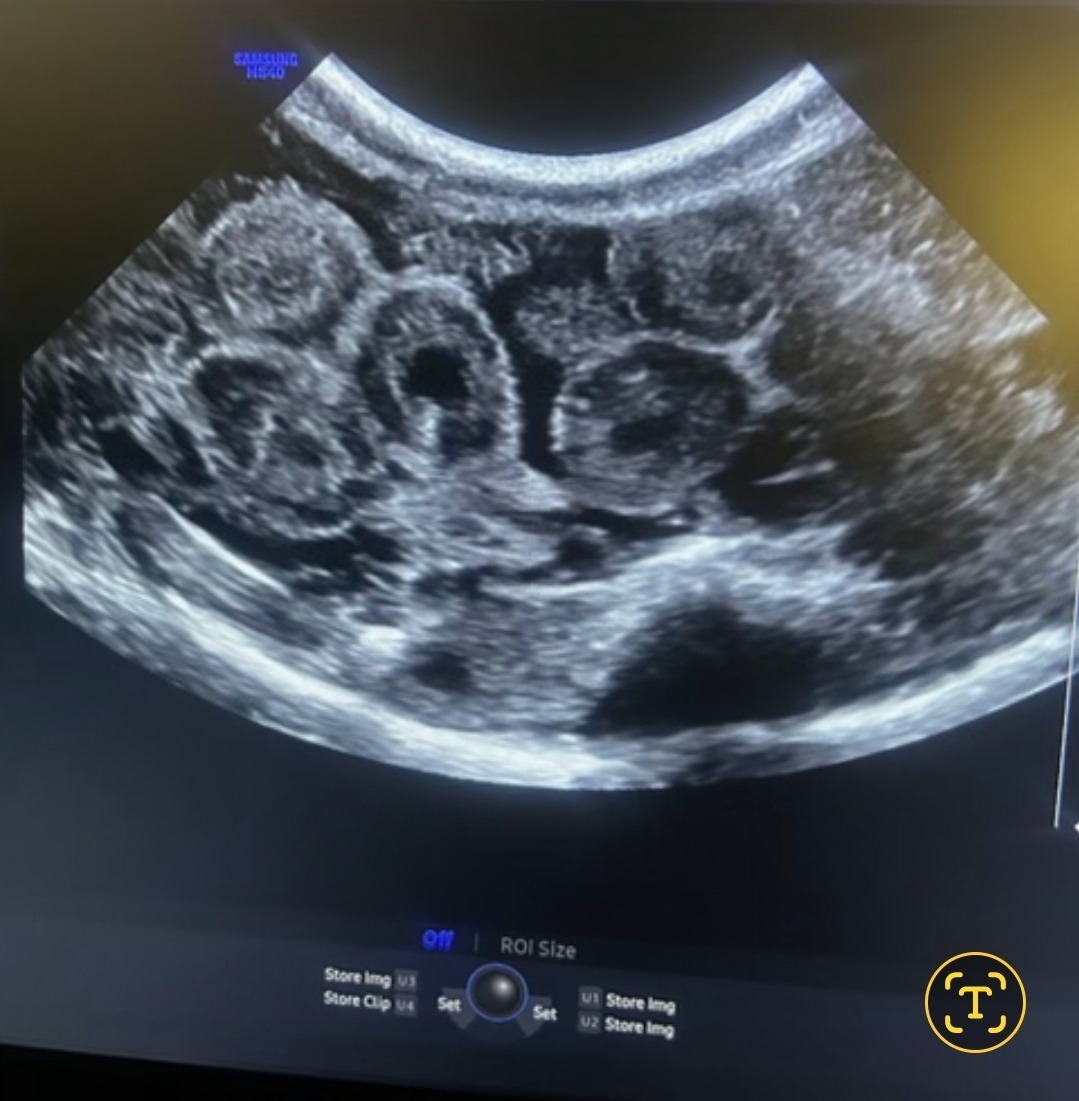

In December, Copper suddenly became swollen and inflamed. After multiple vet visits, X-rays, medications, and bloodwork, we finally received devastating answers. A sonogram confirmed that Copper is actually female and has follicular stasis, with approximately 20 eggs trapped inside her body that she cannot pass on her own.